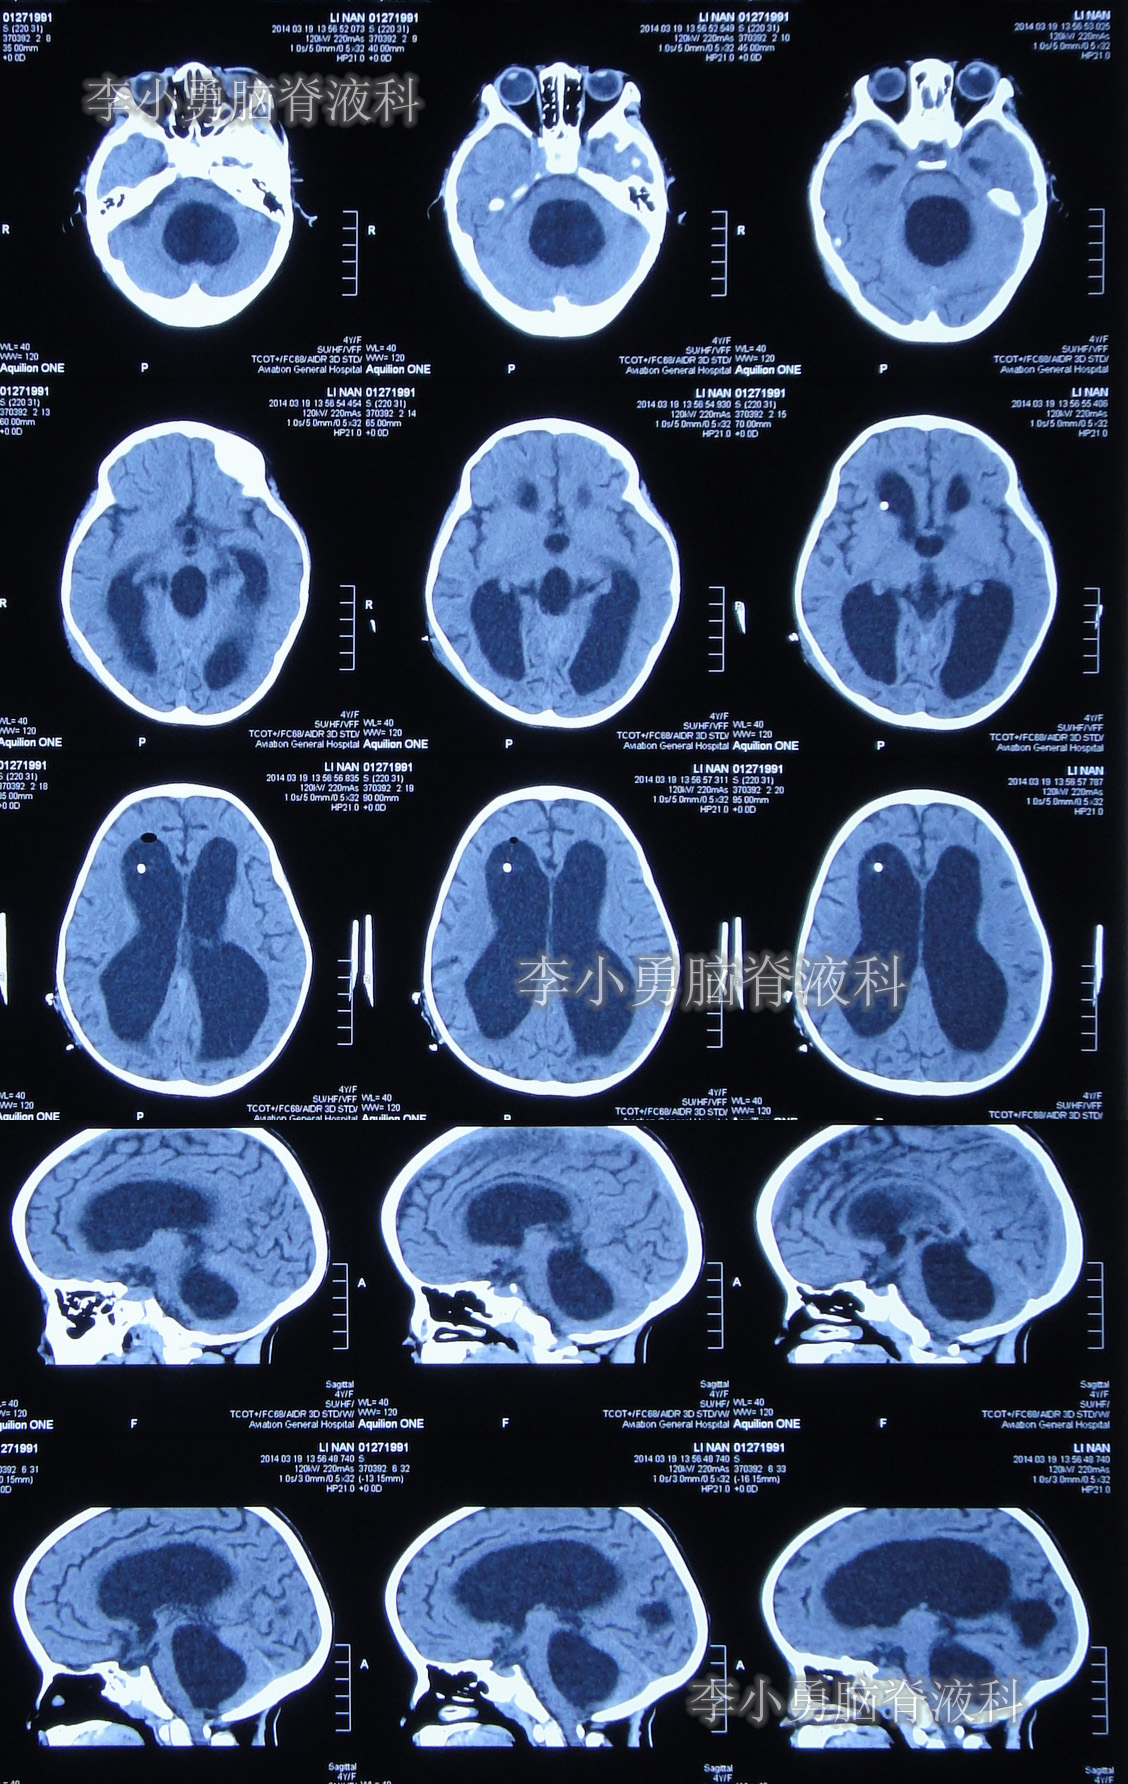

当天头颅CT示第四脑室包括在内的脑室系统全部显著扩张的表现(图-5)。

图-5:2014年3月17日入院时头颅CT

住院治疗第2天即2014年3月19日,复查头颅CT示第四脑室包括在内的脑室系统扩张程度虽均有所减轻,但第四脑室扩张程度仍严重(图-7)。

图-7:2014年3月19日头颅CT